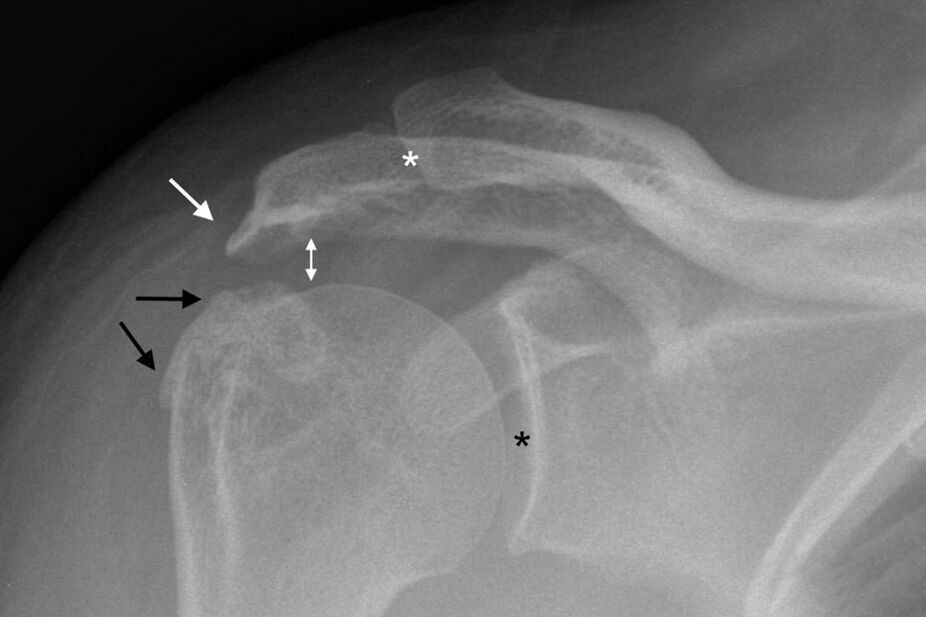

Osteoartritis ramenskega sklepa je mogoče diagnosticirati s standardnim rentgenskim slikanjem rame. Slika je posneta v dveh projekcijah. Zdravnik diagnosticira bolezen ob prisotnosti dejavnikov, kot so:

- Zoženje sklepne špranje;

- Nastanek osteofitov;

- Skleroza kostnega tkiva.